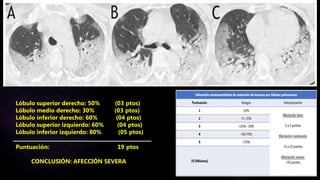

Lóbulo superior derecho: 50% (03 ptos)

Lóbulo medio derecho: 30% (03 ptos)

Lóbulo inferior derecho: 60% (04 ptos)

Lóbulo superior izquierdo: 60% (04 ptos)

Lóbulo inferior izquierdo: 80% (05 ptos)

Puntuación: 19 ptos

CONCLUSIÓN: AFECCIÓN SEVERA

CONCLUSIÓN: AFECCIÓN SEVERA –

CATEGORIA B (PATRÓN EMPEDRADO)